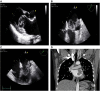

Case summary: A 44-year-old female patient without a specific medical history presented with intermittent dyspnea that started 1 month prior to presentation. A heterogeneous mass was observed in the left atrium on echocardiography and a large mass was observed in the left atrium on computed tomography. Surgery was performed under the suspicion of atypical cardiac myxoma, and the tumor was successfully removed. However, postoperative histopathological examination revealed cardiac osteosarcoma. The patient underwent chemotherapy and has been well maintained without recurrence for 10 years.

Conclusion: We present a case report of the echocardiographic features and treatment strategies for cardiac osteosarcoma, an extremely rare cardiac tumor. Multimodal imaging can be helpful; however, a histological diagnosis through surgical resection is essential. Appropriate treatment and follow-up based on histological findings are necessary.